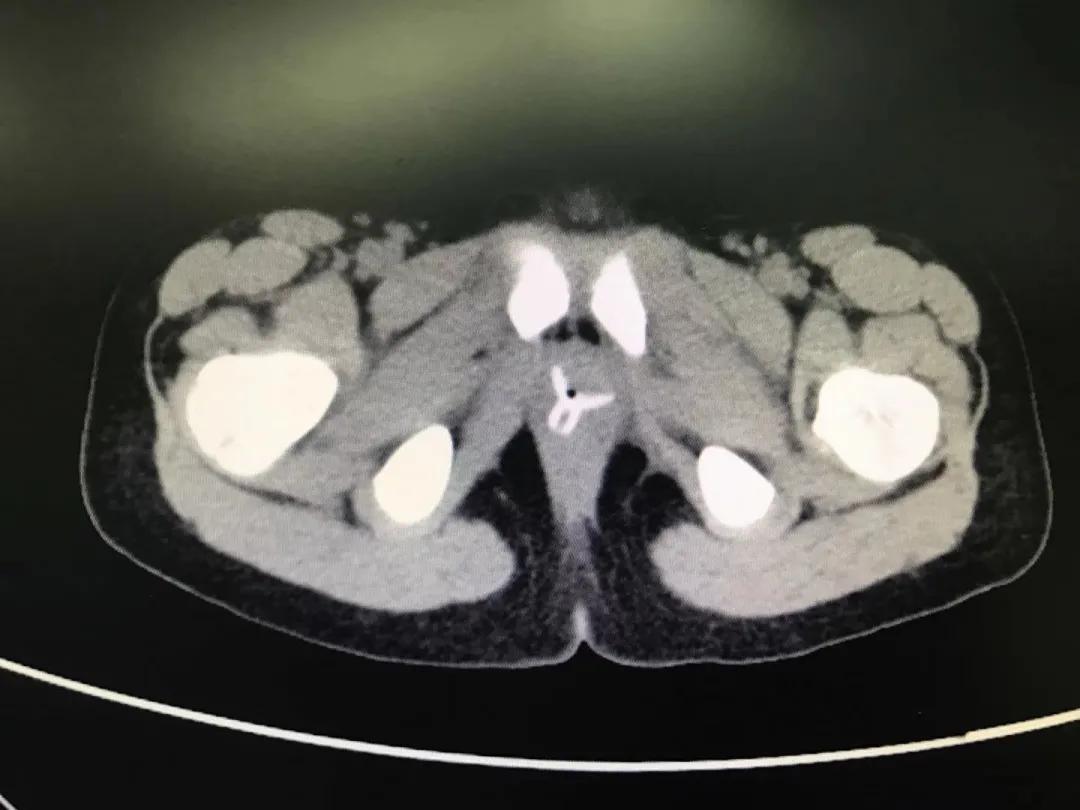

患儿晚上七点多被送至南京市儿童医院,泌尿外科汪俊主治医师立即安排了急诊手术。“幸好玻璃珠并没有进入尿道和膀胱,只是被塞进了*头龟**和包皮之间,包皮水肿造成异物嵌顿,只需将水肿的包皮切开,就可以取出珠子。”

11岁男孩一个多月前,因好奇将12颗磁力珠从尿道塞入。12颗磁力珠在膀胱内紧紧相连,并吸附尿垢,形成一个中间带坚硬“结石”的较大环状异物。最终只能开放下膀胱切开取出异物。